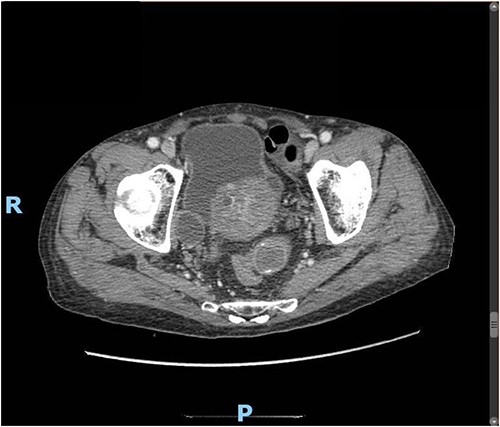

Upon clinical examination, the patient was vitally stable. Abdominal examination revealed a distended abdomen with generalized tenderness. Digital rectal examination revealed an empty rectum with no palpable masses. Laboratory investigations were unremarkable (Table 1). Abdominal X-ray was done (Fig. 2) and showed dilated large bowel loops suggestive of bowel obstruction. Enhanced CT scan of the abdomen and pelvis was obtained (Figs 3–5) and showed a dilated large bowel loop, with air fluid level. A 2.5-cm gallstone was noted, impacting the sigmoid colon and causing partial large bowel obstruction. There was evidence of pneumobilia with air foci within the gallbladder with a suspected fistula with the hepatic flexure.

Enhanced CT scan of the abdomen showing a gallbladder stone impacted at the sigmoid colon, with a significantly enlarged prostate causing narrowing of the rectosigmoid junction (axial view).

Enhanced CT scan of the abdomen showing a gallbladder stone impacted at the sigmoid colon, with a significantly enlarged prostate causing narrowing of the rectosigmoid junction (sagittal view).